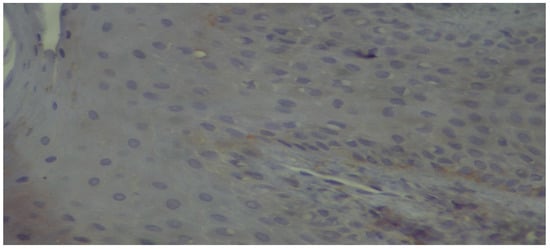

| Staining Pattern | Periodontal Disease and Diabetes (Test Group) | Periodontal Disease Only (Control Group) | p-Value |

|---|---|---|---|

| Negative | 9 (69.2%) | 7 (77.8%) | |

| Focal Mild Positivity | 2 (15.4%) | 1 (11.1%) | |

| Diffuse Mild | 1 (7.7%) | 1 (11.1%) | |

| Diffuse Moderate | 1 (7.7%) | 0 (0.0%) | |

| Non-applicable/Missing | 0 (0.0%) | 0 (0.0%) | |

| Chi-square test | 0.544 |